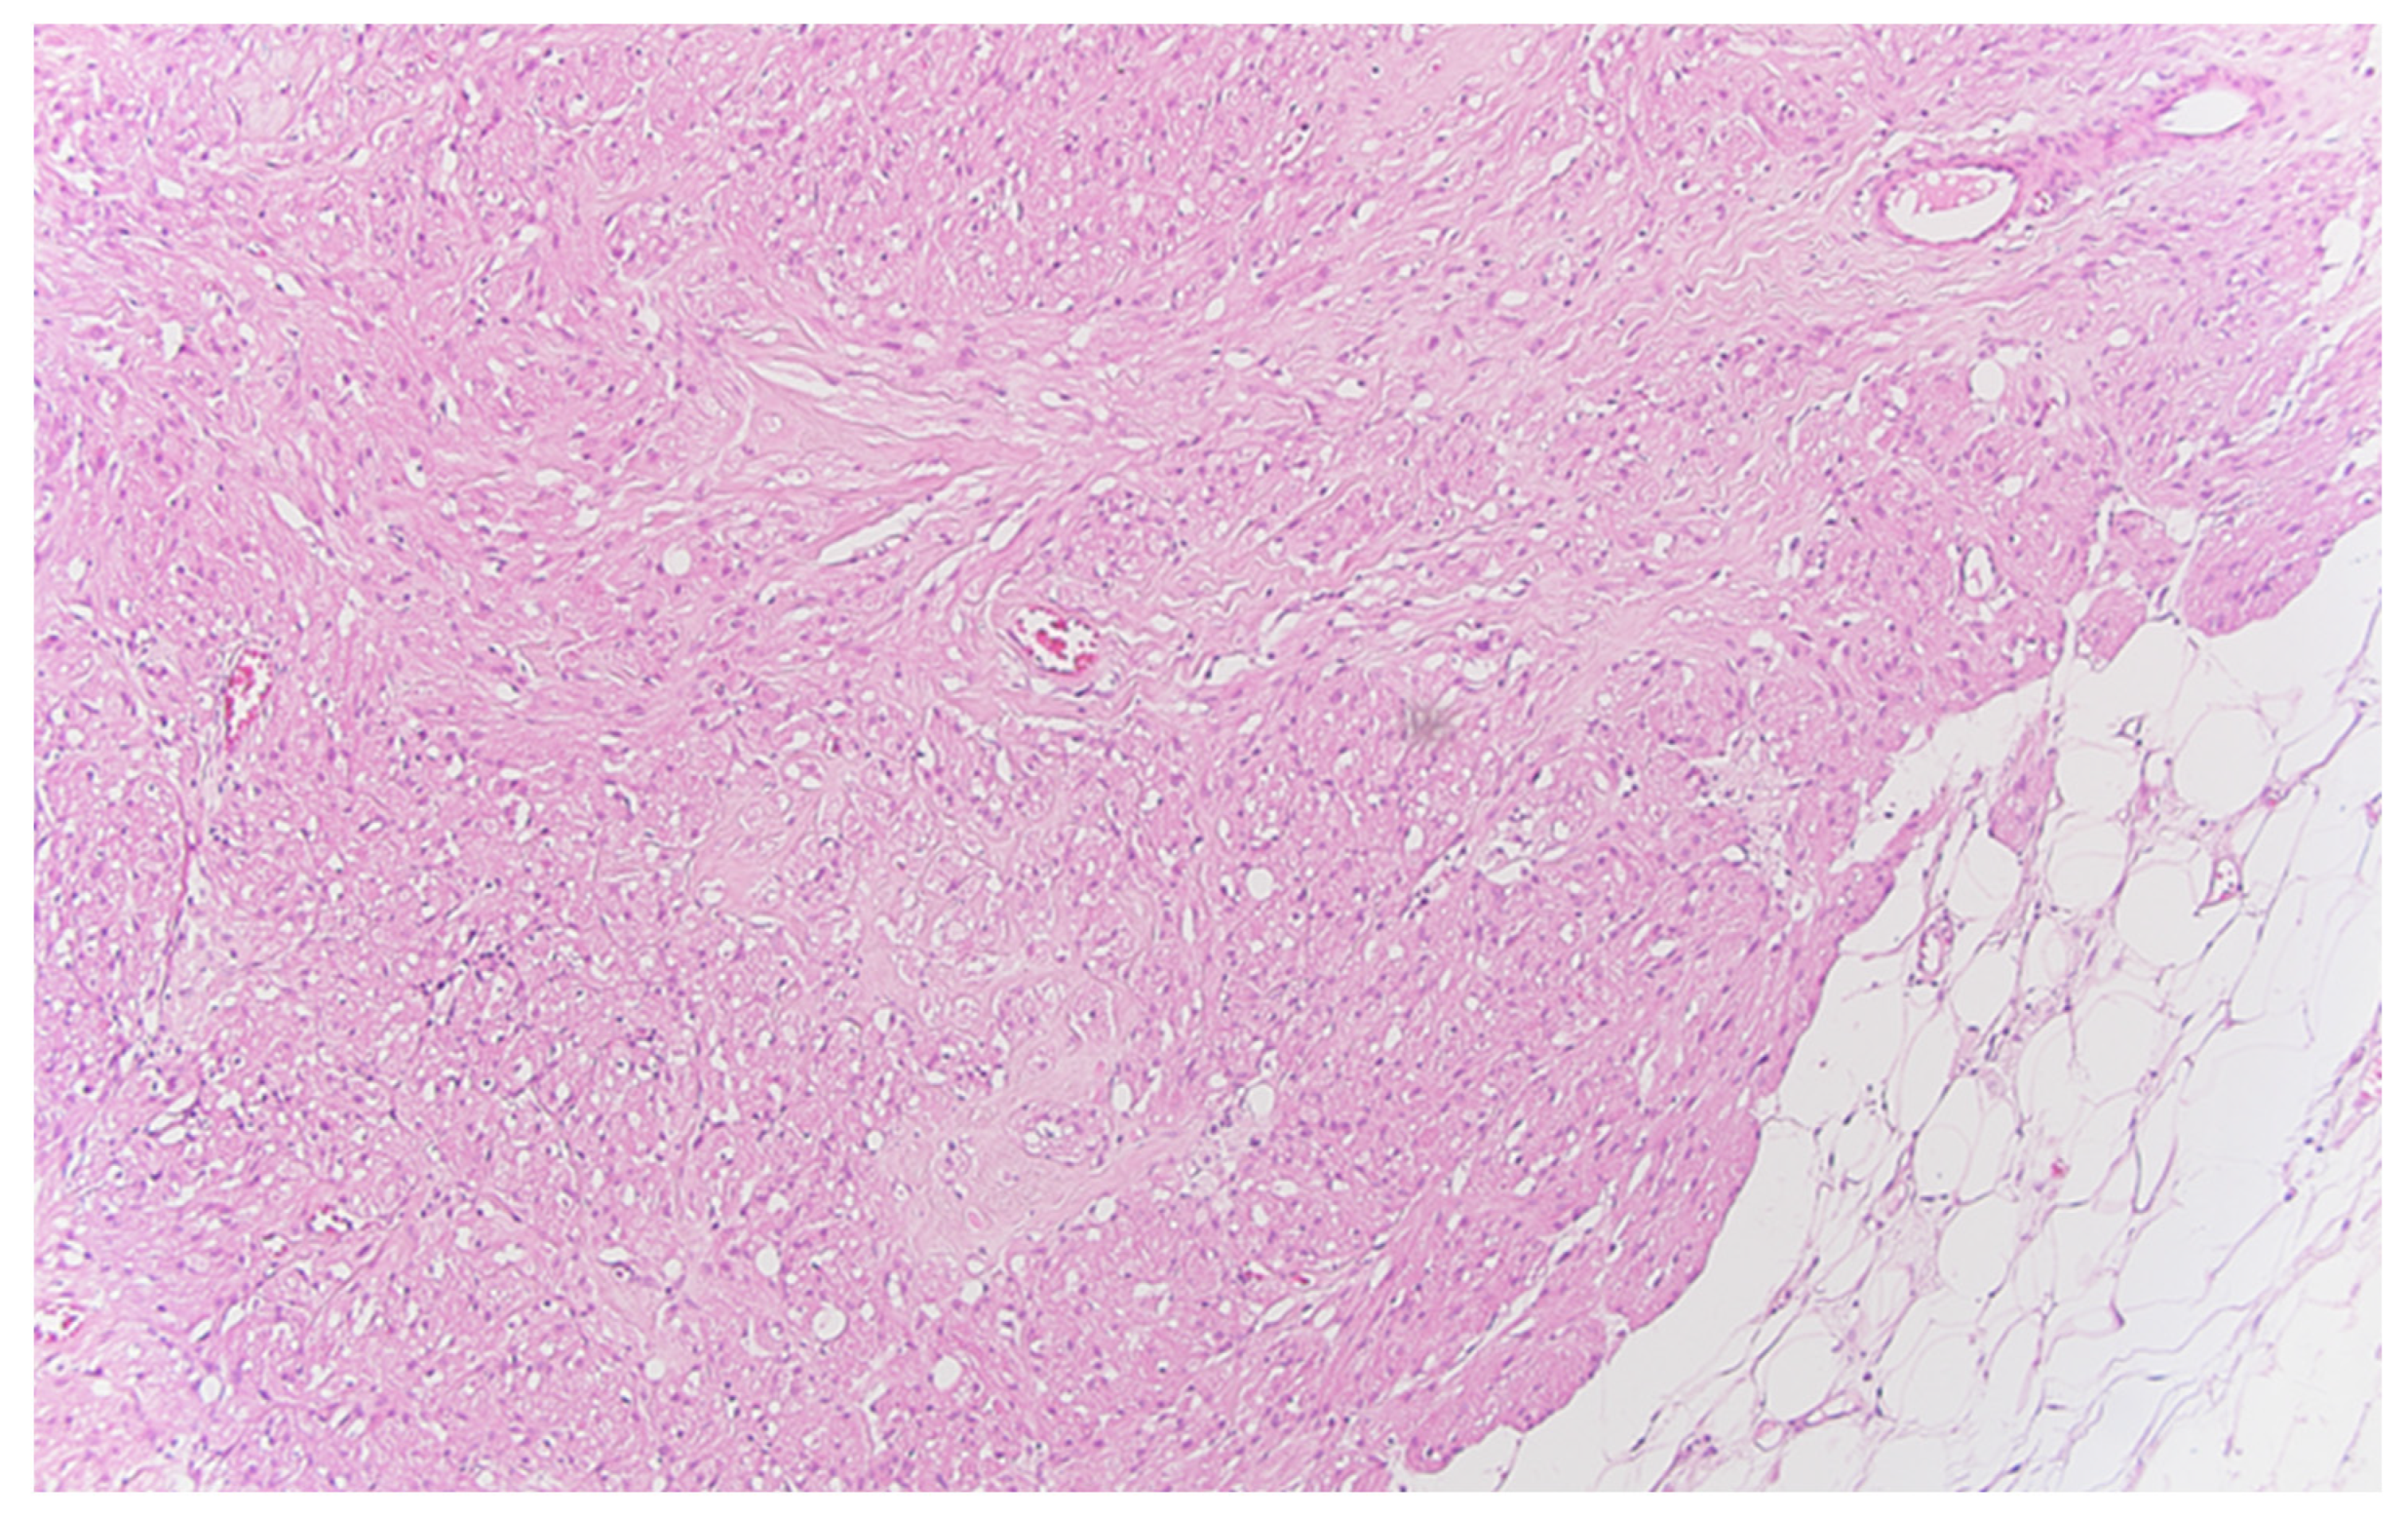

Serial sections of the ascending colon tumor reveal massive infiltration of a diffuse, mucinous carcinoma, with predominantly intracellular secretion of mucin (“signet-ring” cells); some isolated aspects of mucinous tubular adenocarcinoma are also observed. The tumor is ulcerated on the surface, extensively invades the submucosa (Figure 1), and dissociates the muscular layer (muscularis propria), being found massively in the subserosa (Figure 2), with perforation of the visceral peritoneum: tumor cells in ink or less than 1 mm from the inked serosa (pT4a); numerous lymphatic tumor emboli, with frequent aspects of perineural invasion. Of 26 lymph nodes, 24 show massive carcinomatous metastases (adenocarcinoma type, Figure 3)—pN2b.

Figure 3.

Regional lymph node metastasis of the colon carcinoma, with adenocarcinoma pattern in the afferent lymphatics and subcapsular sinuses, HE ×200.

Well delineated from the previously described malignant epithelial–glandular tumor, large polygonal cell nodules, with abundant, eosinophilic, granular cytoplasm, hyperchromatic, or vesicular nucleolated nuclei are found in the submucosa of the cecum and the visceral peritoneum of the ascending colon (Figure 4); without cyto-nuclear atypia, without tumor necrosis. These tumor nodules develop in the vicinity of nerve fibers.

Figure 4.

Peritoneal granular cell tumor nests and fascicles of large polygonal cells with abundant, eosinophilic, granular cytoplasm, HE ×100.